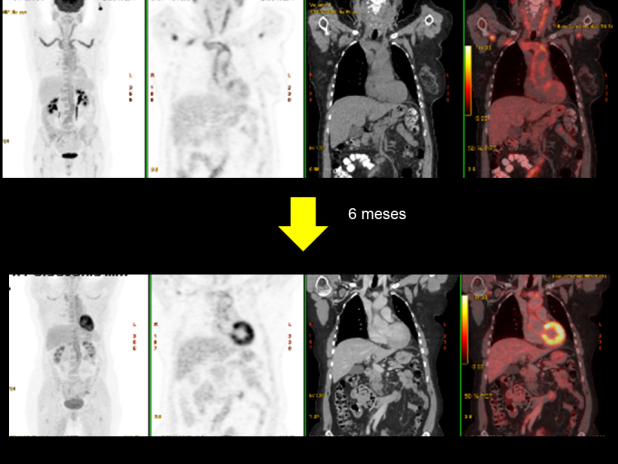

Se realiza PET-CT de control a los 6 meses de iniciado el tratamiento, que muestra respuesta morfo-metabólica parcial, con disminución de la actividad en grandes vasos incluyendo arteria temporal derecha y mejoría radiológica de las alteraciones inflamatorias circundantes (Figs. 4 y 5). Los datos cuantitativos comparativos (SUV) son los siguientes:

- Cayado aórtico (previo SUV 7.5, actual 3.5).

- Troncos supraaórticos y divisiones (previo SUV 6.3-7, actual 4.4).

- Carótidas comunes (previo SUV 5, actual 3.1).

- Aorta abdominal (previo SUV 4.6, actual 4.1).

- Ejes ilíacos (previo SUV 4.6, actual 3.2).